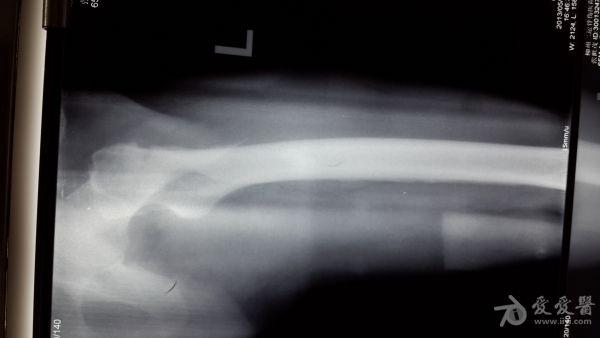

股骨粗隆间粉碎特性骨折的手术方案

男性,65岁